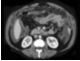

85.患者,女,36岁。低热、乏力,腹胀不适1月余,结合影像学检查,应考虑为()